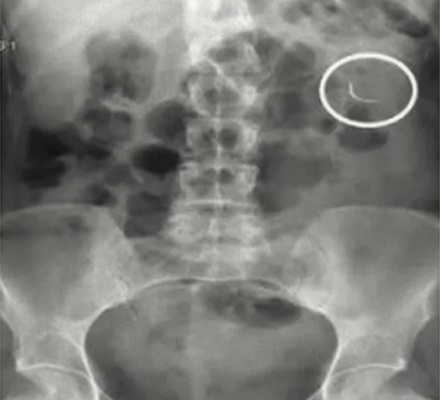

如果少了一根针,在找到它之前,所有医务人员都不能离开手术室,超过 1 小时还是没找到甚至要动用 x 线透视。